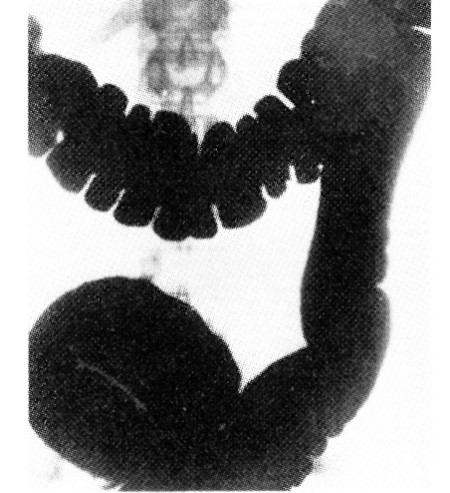

●第10回『化学学校記事』情報公開裁判 ●帝銀事件と登戸研究所 ●第19回「衛生学校記事」情報公開裁判 ●シンガポールで、731部隊は何をやっていたのか? ●731部隊『留守名簿』(不二出版)2018年9月 ●京大 軍医博士論文の検証 ●731部隊『留守名簿』公開 ●ある元自衛官の回想 「化学学校の黒い霧」 ●第10回ビザ発給拒否・集会妨害国賠訴訟【9月21日(金)11:30〜東京地裁415号室】 ●731部隊と「要塞」遺跡を訪ねる 元731部隊軍医と強制不妊手術 「明治150年」史観批判ー近現代日本の戦争・植民地支配と国民統制ー山田朗、他 中国の侵略被害者の証言を聞く集い2018 11.30 ●お知らせ ![]() ![]() 京大の「731部隊」論文疑惑(上) 勝間田秀樹(京都支局) 731部隊将校の学位取り消しを 人体実験疑い論文で京大に 「特殊部隊731」 秋山 浩著 (三一書房 1956年6月30日 発行) 職種不明の軍属 そのとき、折悪しく空襲に見舞われ、一時は出発が危ぶまれたのだったが、特命の軍属であるからというので、予科練終生たちを運ぶ列車に便乗して、下関に着き、九州や四国、中国、関東、関西の人たちと合流した。 ところが、朝鮮海峡の制空制海権は敵の手に奪われていたので、丸2日待っても連絡船が来ないのである。私達30人ばかりの少年たちは、仲野雇員と、関東地方の募集係である大角雇員の指揮で、漁船をやとって博多へ移動した。 その頃から、私達の気分は沈みがちになっていた。自分たちの行動には、何か隠密めいたものがつきまとっていることを、誰もが感知し始めていた。むつましく語り合うことすら避けなければならないような気持ちから、同じ運命に釘付けられているにも関わらず、まだ誰とも親しみがわかなかった。 北九州は、ちょうど、桜が満開であった。しかし、博多の海岸には、船を待つ人々がごった返していて、花などに気をとられている余裕はなかった。 ようやく沖合いに、2隻の白い船が現われた。3月31日の朝である。博多は埠頭がなかったので、私達はハシケに分乗して船までいたり、救命具のつけ方を教えられた。だが、船は一向に出帆する様子はなく、またしても不自由な船の中で待たされることとなった。 ![]() 「元満州中川村開拓団 私の敗戦回顧録」 日本は、日中戦争で国際法に違反して、毒ガス戦、細菌戦、無差別爆撃を行った。日本政府は、この事実をきちんと認めていない!! ●『日本の中国侵略と毒ガス兵器』 歩平著(山邊悠喜子、宮崎教四郎訳)明石書店より 第2章 地図から消えた神秘の大久野島 記録1 今日の大久野島 山を通り抜け、車は瀬戸内の海辺にやってきた。明るい海は平静そのまま、港に停泊している大小様々な船、船、遠く近く浮かぶ島々がはっきりと見える。以前私は瀬戸内海は海水汚染が進んでると聞いていた。沿岸の漁民は海の資源が日増しにすくなくなったことで、悩んでいたというが、今はどうなのだろうか?同行の日本の友人は、「もう汚染処理を行ない、現在漁業はとても順調だ」と、説明した。この時、運転手が遠くに見える高い山が大久野島だと教えてくれた。私はその山の上に高い鉄塔を認めた。 ●特集 軍拡に走る安倍政権と学術① 15年戦争中の「医学犯罪」に目を閉ざさず、繰り返さないために 1、戦争における医学者・医師たちの犯罪 西山勝夫さん(滋賀医科大学名誉教授)に聞く にしやま・かつお=滋賀医科大学名誉教授、 15年戦争と日本の医学医療研究会事務局長、「戦争と医の倫理」の検証を進める会代表世話人、軍学共同反対連絡会共同代表 5、いまどんな議論が必要か ■日本ではまだ広く知られていない戦争医学犯罪 ―現在、日本では、どのような議論がなされているのでしょうか。また、いま、軍事研究への大学や研究機関の動員という問題が大きな問題となっているときに、どんな議論がなされる必要があるとお思いですか。 しかし、ナチス・ドイツの戦争医学犯罪を踏まえて、世界医師会はジュネーブ宣言や医の国際倫理綱領で「医師は、常に何ものにも左右されることなくその専門職としての判断を行い、専門職としての行為の最高の水準を維持しなければならない」などの条項を採択し、「患者の人権擁護」のためには患者、医師、医師会、それぞれの自律が必要だとしてきました。このような国際的に普遍的な考え方にたつならば、国政の如何などとは関係なく、日本の医学界・医療界が自省の議論を尽くす必要があります。 ●『人間の価値』 ―1918年から1945年までのドイツ医学 Ch.ブロス/G.アリ編 林 功三訳 ■ある大学講師のおこなった人体実験 ベルニングが飢餓実験をした捕虜の写真 ![]() ベルニングの書物『栄養障害』(ティーメ社刊 1949年)にはオリジナルの署名入りで、「造影された大腸。造影剤は3リットルを要した。大腸の内径は大きい。とりわけ下降する部分、シグマ形の部位で弛緩が目立っている」と書かれている。 ![]() ●イタイイタイ病を究明した男 萩野昇 ●驚愕!御用医学者をさかのぼると、すぐに731部隊に行き着く 水俣病問題 ●小島三郎国立予防衛生研究所所長の過去 ●小泉親彦と宮川米次の絆 ●ヒロシマからフクシマへ ●宮川正 ●「想定外」 と日本の統治—ヒロシマからフクシマへ— ●ビキニ「死の灰」世界各地へ ●自衛隊とサリン ●相模海軍工廠・寒川と平塚にあった秘密毒ガス工場 ●日本の国家機密 ●兒嶋俊郎さんを偲ぶ ●ニュース トランプ氏元側近に禁錮3年、米連邦地裁が判決 NHKで森友事件を取材していた記者 上層部の意向で報道が縮小した経緯明かす 旧優生保護法「出産できる体に戻して」知的障害者女性が訴え 靖国神社でぼや 中国籍の男女を建造物侵入容疑で逮捕 「南京事件」に抗議 警視庁 日大医学部、卒業生の子を優遇 「入学意識が高い」 憲法9条を守れ!! 「空母化」ありき 現場困惑 政府、違憲否定「F35B常時は搭載せず」 「水俣病は終わらない」公式確認から60年―私たちに託されたメッセージ 松本元死刑囚らの死刑執行文書、ほぼ全て黒塗りで開示 “旧優生保護法”強制的な不妊手術 事業として推進(18/04/27) 真相を解明していないからこうなるのだろう!! オウム13人死刑で「上川陽子法相」一生SPつきの生活 ●昭和天皇の戦争責任を問う!!大嘗祭反対!! ●昭和天皇(ハーバード・ピックス著『昭和天皇』より) 第3部 陛下の戦争 1931(昭和6)年―1945 (昭和20)年 第7章 満州事変 この政策の転換は 東京の参謀本部がソ連軍との衝突を恐れ軍の北部満州への侵攻を抑えようとしていたときに行われた。11月5日、昭和天皇は金谷参謀総長に特別に委任命令権を与え、〔本来、天皇に直隷する〕関東軍の作戦と用兵に関する「細小事項」を金谷が決裁することを許可した。関東軍が鉄道により北部満州を移動する間の3週間、金谷は現地部隊の行動を監督するためさまざまな機会にこの特別な権限を5回、行使した〔「臨参委命」という形式での参謀総長命令のこと〕。 他方、アメリカのスティムソン国務長官の勧告を受けて、連盟理事会は日中双方に対しケロッグ=ブリアン協定〔不戦条約〕を発動した。そして、日本代表団の異議に対して連盟理事会は、11月16日を期限として占領地からの部隊の撤退を日本に求める道義的決議を可決した。海外では日本の侵略に対する批判が高まったが、新聞、ラジオ、興行界、帝国在郷軍人会に先導され、日本の世論は関東軍を支持し、中国と西洋を非難していた。南満州鉄道株式会社総裁内田康哉が、関東軍と呼応して満州で中国の新体制確立を呼びかけようと東京を訪れると、群衆は彼を熱狂的に迎えたのであった。 ●小泉親彦と昭和天皇 ●近現代史を《憲法視点》から問う〜「湘南社」の憲法論議〜 ●近代天皇制の真髄は ●福沢諭吉 ●神武と戦争 ●日本国憲法第9条 1、日本国民は、正義と秩序を基調とする国際平和を誠実に希求し、国権の発動たる戦争と、武力による威嚇又は武力の行使は、国際紛争を解決する手段としては、永久にこれを放棄する。 2、前項の目的を達するため、陸海空軍その他の戦力は、これを保持しない。国の交戦権は、これを認めない。 憲法9条を生かそう!! |